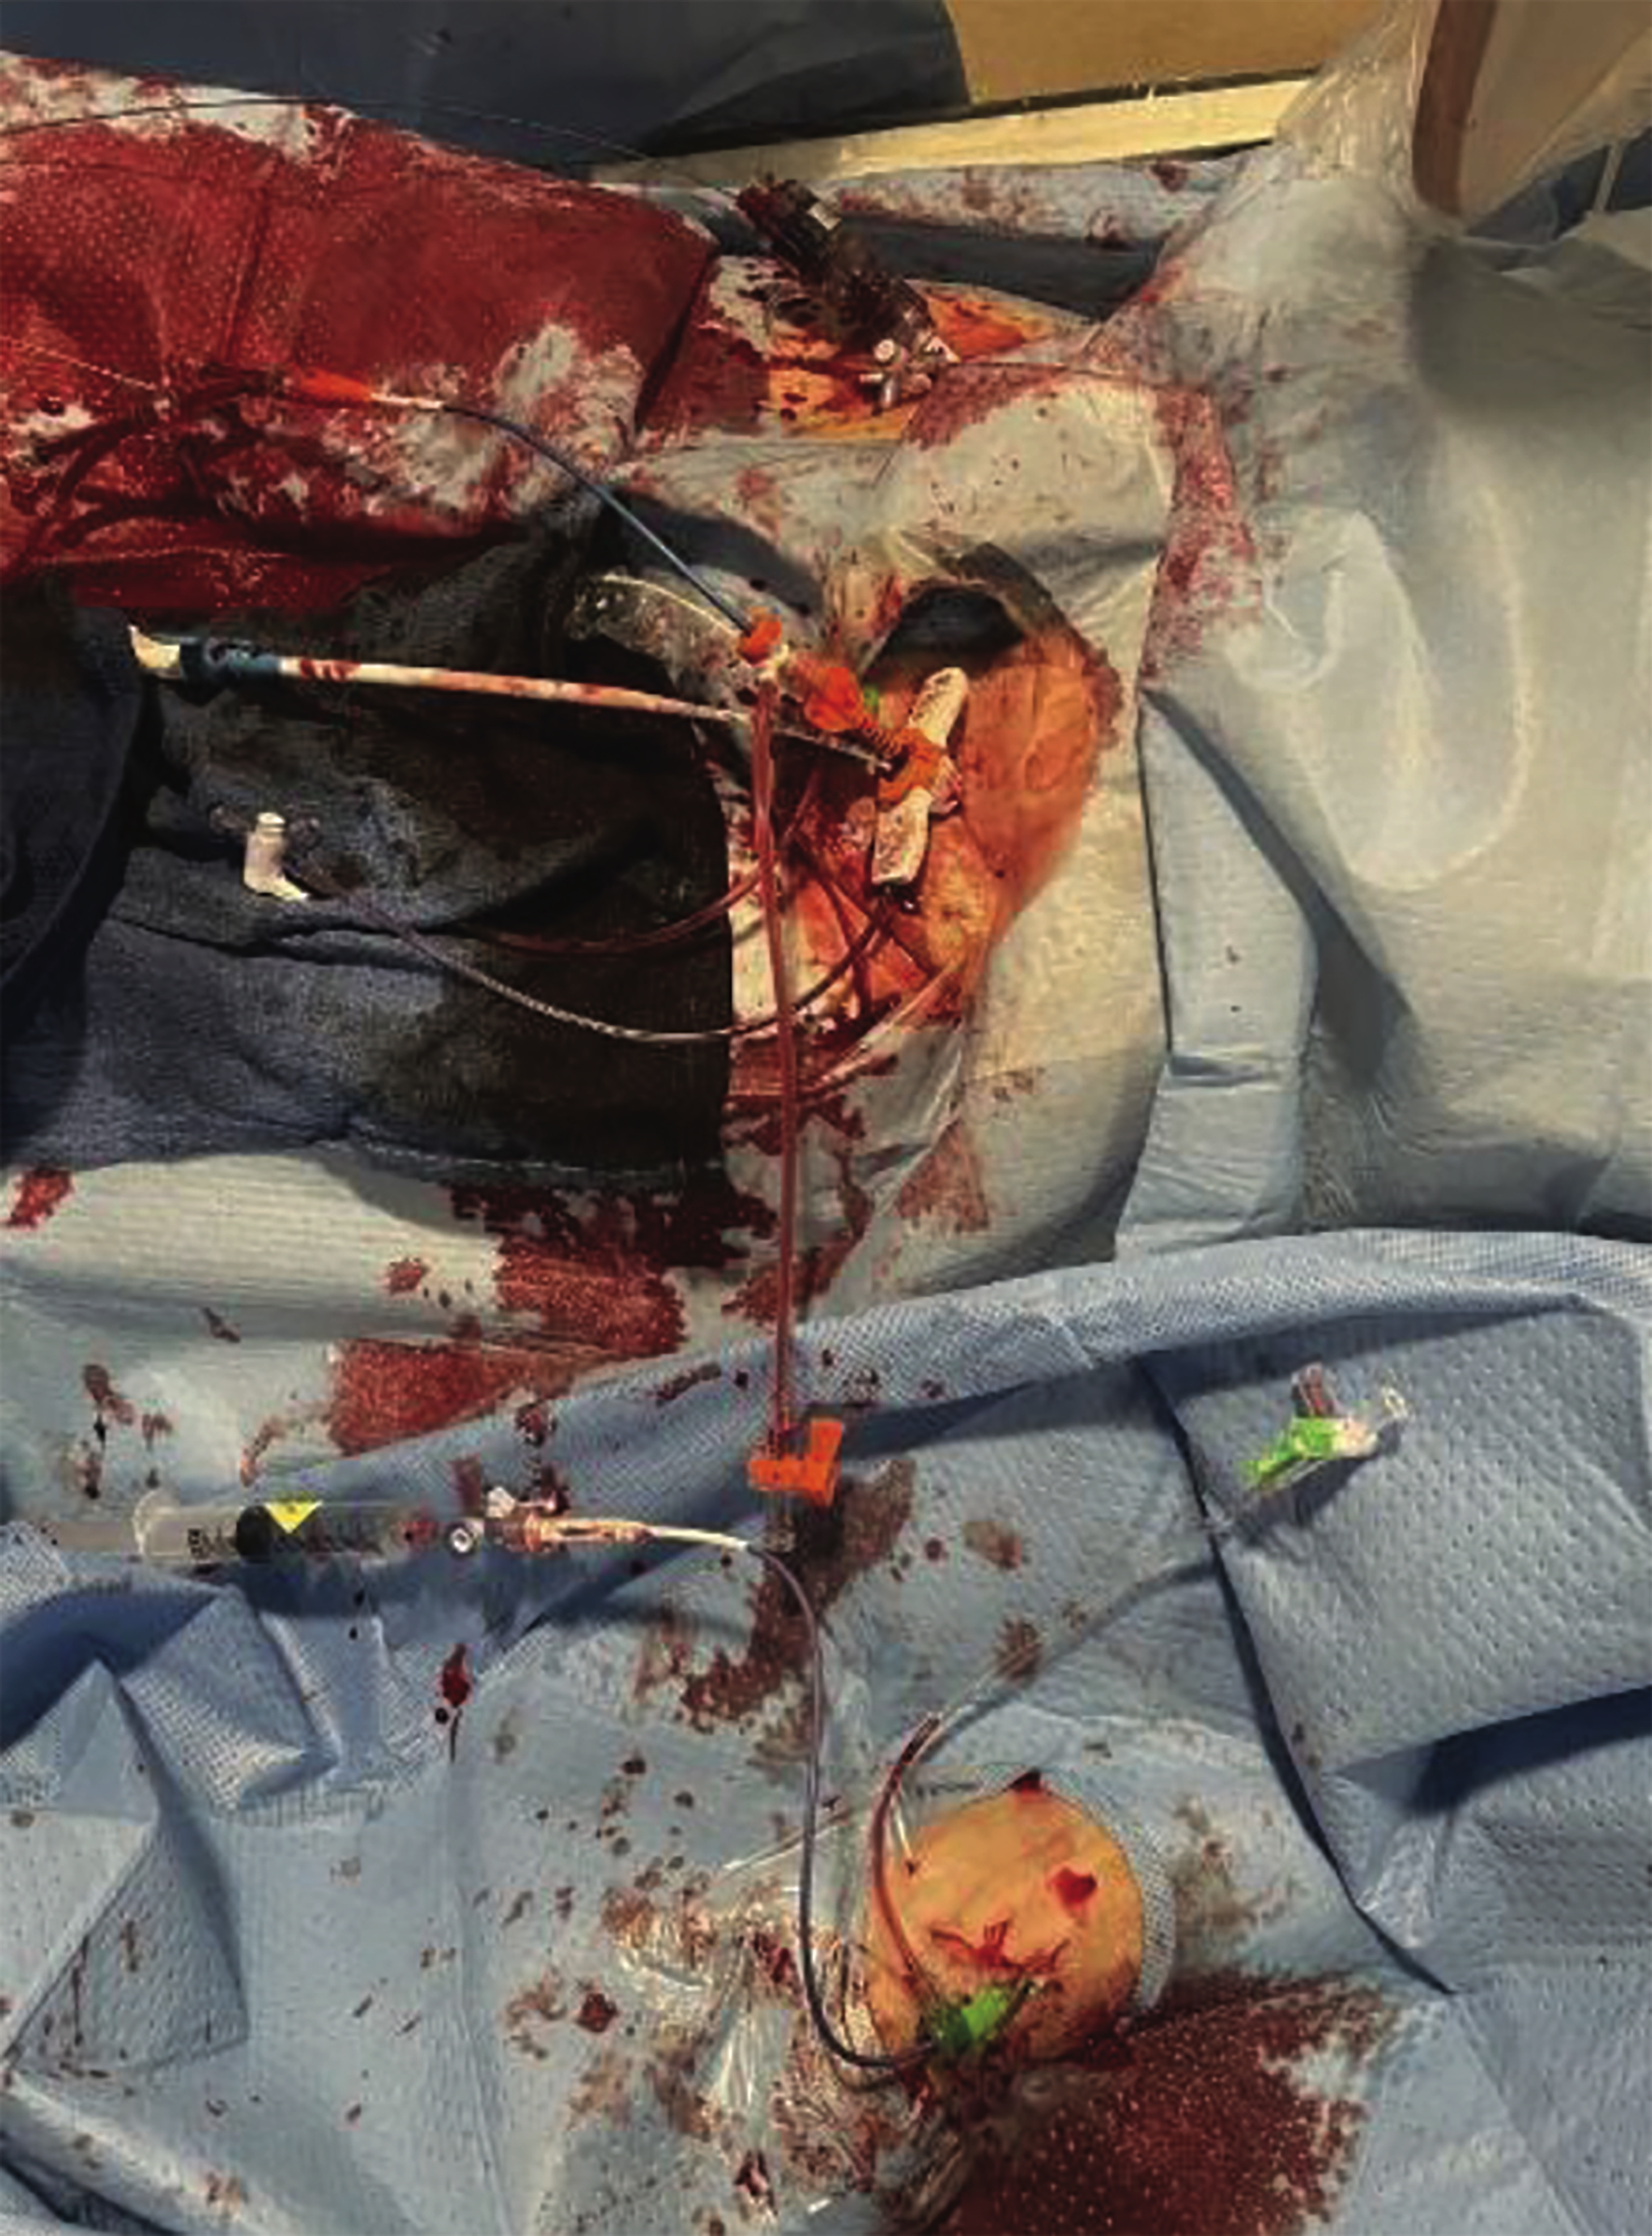

Pre-procedural planning included the use of a heart team approach, including cardiology, cardiothoracic surgery, and anesthesia. The patient was monitored closely, and given his diastolic heart failure, an Impella percutaneous circulatory support device (Abiomed) was utilized to ensure hemodynamic stability during the procedure. The procedure began with transvenous pacing wire insertion via the left femoral vein. Bifemoral and left radial access were established with 6 French sheaths (Figure 2), allowing the team to “alternate” (or “ping-pong”) between coronary intervention and valve delivery without exchanging catheters or losing support. A 7 French sheath was inserted for coronary stenting. The Impella device was placed in the left ventricle to provide circulatory support during the PCI, particularly given the patient’s severe CAD and the anticipated hemodynamic instability from his underlying heart failure (Figure 3).